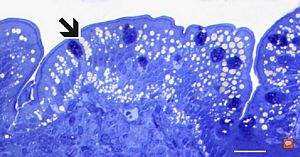

F,52y. | spirochetosis … colon (HE) … blue-stained brush border

F,52y. | spirochetosis … colon Warthin-Stary silver impregnation

F,52y. | spirochetosis - colon